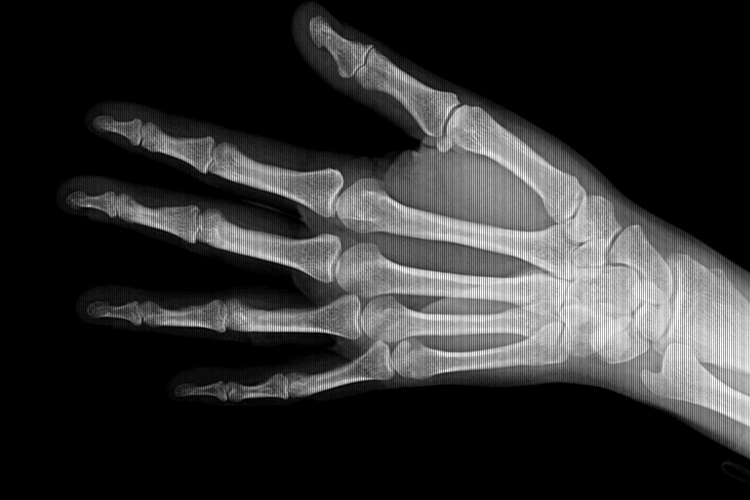

正常左手手腕X光片可见桡尺骨远端、8块腕骨和5个掌骨的近端,以及相互构成的关节。

正常左手手腕X光片可见正常的骨骼结构,包括桡尺骨远端、8块腕骨和5个掌骨的近端,以及其相互构成的桡腕关节、腕骨间关节及腕掌关节,且骨骼以及相互连接组成的关节无变形、无畸形。